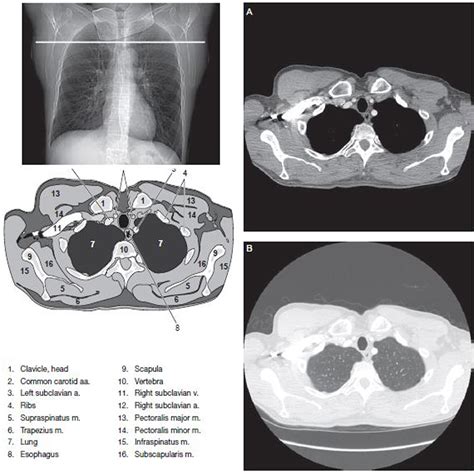

A computed tomography (CT) scan combines a series of X-ray images taken from different angles around your body. A computer then processes these images to create cross-sectional views, or "slices," of the bones, blood vessels, and soft tissues inside your chest. Unlike a standard X-ray, which provides a two-dimensional overview, a chest CT scan offers much greater detail, making it an indispensable tool for identifying abnormalities that might otherwise go unnoticed.

When your radiologist reviews the images, they are looking for deviations from a normal chest CT scan. A "normal" result essentially means that the structures visualized within the scan appear healthy and do not exhibit signs of disease, such as tumors, infections, inflammation, or structural irregularities.

If you have received a report indicating your scan is normal, you might see medical terminology that seems confusing. Radiologists use structured language to describe what they see. A normal chest CT scan report typically indicates that the following structures are within normal limits:

• Lungs: No evidence of nodules, masses, infiltrates, or signs of pneumonia or scarring.

• Mediastinum: This is the central compartment of the chest. A normal scan shows that the heart size is within normal limits, and major blood vessels (like the aorta) do not show aneurysms.

• Lymph Nodes: There is no significant enlargement (lymphadenopathy) of the lymph nodes in the chest.

• Pleura: The lining of the lungs is thin and free of fluid (pleural effusion) or thickening.

• Bones: The visible portions of the ribs, spine, and sternum appear healthy without fractures or suspicious lesions.